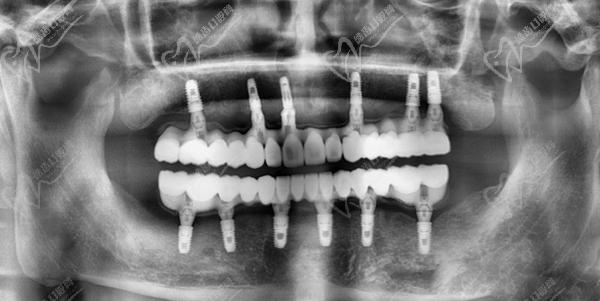

4、植入種植體佩戴牙冠:根據(jù)預(yù)先設(shè)計(jì)好的種植牙方案,在拔牙后的創(chuàng)口內(nèi)植入選定的種植體,確保種植體與牙槽骨緊密結(jié)合,并佩戴臨時(shí)牙冠,實(shí)現(xiàn)當(dāng)天種牙、當(dāng)天用牙。

全口即拔即種即刻負(fù)重種植牙一般分為兩期,一期手術(shù)是在拔除牙齒后立即植入種植體,戴臨時(shí)牙冠,等待創(chuàng)口愈合;二期手術(shù)則是待創(chuàng)口愈合后,進(jìn)行固定牙冠佩戴。全口即拔即種即刻負(fù)重可以同時(shí)全口做,也可以先上頜后下頜。在每期手術(shù)之間,醫(yī)生會根據(jù)患者的具體情況進(jìn)行相應(yīng)的藥物治療和護(hù)理指導(dǎo)。

牙友1、前天結(jié)束的全口種植牙,拔牙加同期種12顆瑞士士卓曼,即刻負(fù)重!全口牙周炎伴隨多顆牙松動且骨量不足等問題,普通的種植手術(shù)無法滿足生活需求,想要做即拔即種即刻戴上臨時(shí)牙,因?yàn)槌R?guī)的植骨手術(shù)需要等待很長時(shí)間。經(jīng)過正規(guī)醫(yī)院骨質(zhì)評估分析,上頜AO4+兩邊穿翼手術(shù),患者手術(shù)結(jié)束當(dāng)天就可以正常用牙,本人表示非常高興和滿意!感謝醫(yī)院團(tuán)隊(duì)協(xié)作!

圖是我的臨時(shí)牙冠,即拔即種的牙冠都是臨時(shí)的,后期要來重新裝